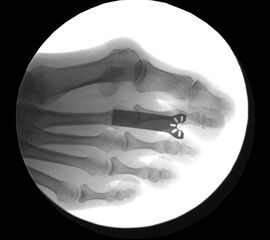

Durch eine maximale Plantarflexion der Zehe kommt es zu einer Reposition des osteotomierten Köpfchens, da die intakten Seitenbänder einen entsprechenden Zug ausüben. Dies kann noch durch einen retrokapitalen Druck unterstützt werden. Das Köpfchen wird mit einer entsprechend großen Klemme oder Fasszange positioniert, unter Berücksichtigung einer eventuell notwendigen Rotationskorrektur. Bei korrekter Gelenkflächenstellung wird die Osteotomie komprimiert, hierbei ist dringend darauf zu achten, dass die Hohmann-Haken nicht im Spalt der Osteotomie einen kompletten Knochenkontakt des Köpfchens verhindern. Dies ist vermutlich der Hauptgrund für verzögerte Knochenheilungen oder Luxationen des Köpfchens in der Aufbelastungsphase. Sofern diese Punkte kontrolliert wurden erfolgt die Fixation des Köpfchens, hier durch Vorbohren mit einem 1,6 mm Draht und einer 2,0 mm Titanschraube.

Die Korrekturosteotomie nach Weil ermöglicht durch eine von distal dorsal nach plantar proximal verlaufende metaphysäre Osteotomie eine Druckentlastung und Weichteil­entspannung des jeweils operierten Strahles. Diese Osteotomie kann als Einzeleingriff oder als Teil einer komplexen Vorfußkorrektur angewendet werden. Nach der Verschiebung des Mittelfußköpfchens wird dieses über eine Mini-Osteosynthese wieder fixiert, das MTP Gelenk wird hierbei mobil erhalten, die Gelenkkapsel wieder verschlossen und die Strecksehnen rezentriert.

• Kontrollierte Korrektur des Vorfusses mit einer entsprechenden Osteosynthese durch Schrauben oder Drähte.